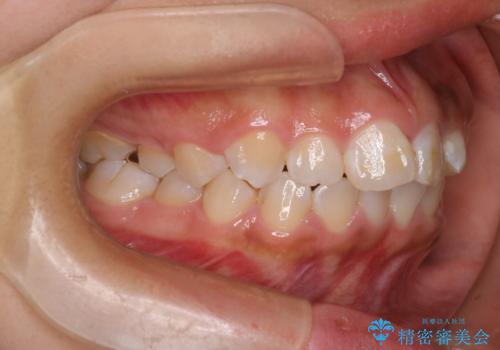

20代女性 八重歯の抜歯矯正

- 右上の第2小臼歯単独抜歯により八重歯を解消する計画としました。

左上の犬歯が元々無いとのことで、第1小臼歯を犬歯と見立てる計画となっています。顎間ゴムなどの協力度も高く、順調に治療を終えることができました。